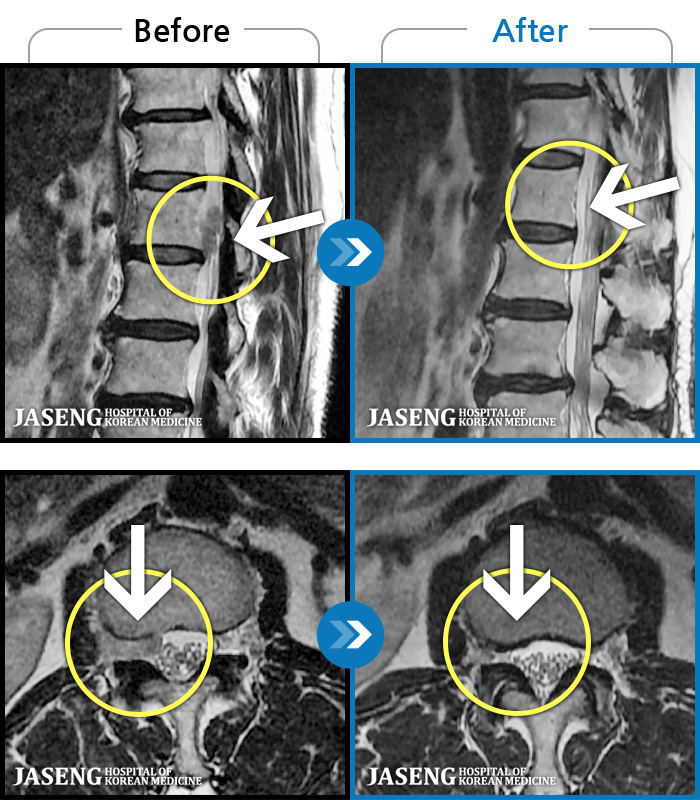

저는 교통사고 후유증과 운동부족,잘못된 자세등으로 간혹 허리가 아팠습니다.. 근데 최근 몇일간 무리한후에 허리가 아프고 왼쪽 하지방사통과 저린감이 너무 심하여 밤에 잠도 제대로 들기 어려울 정도 였습니다...MRI를 찍으니 디스크라고 하더라구요..ㅠ..ㅠ 예상은 하고 있었지만 20대후반에 디스크라니...좌절감과

우울감이 심하였습니다.. 무조건 수술은 안하리라는 생각에 원장님을 찾아뵈었습니다..저한테는 어떻게보면 행운이였나봅니다...

앞으로 치료계획에 대해 상세히 설명해주시며 믿음과 희망을 주셨습니다 ..마음이 한결 가벼워 졌습니다..

추나, 침, 약침, 물리치료, 약물(한약)요법을 병행하며 현재 2주가 조금 지났는데...저도 놀랄정도로 왼쪽 하지방사통은 거의 없어졌어요..감동감동 ㅠ..ㅠ

치료에 대해 믿음이 있었지만 이렇게 빨리 회복이 될지는 저도 놀랐습니다...